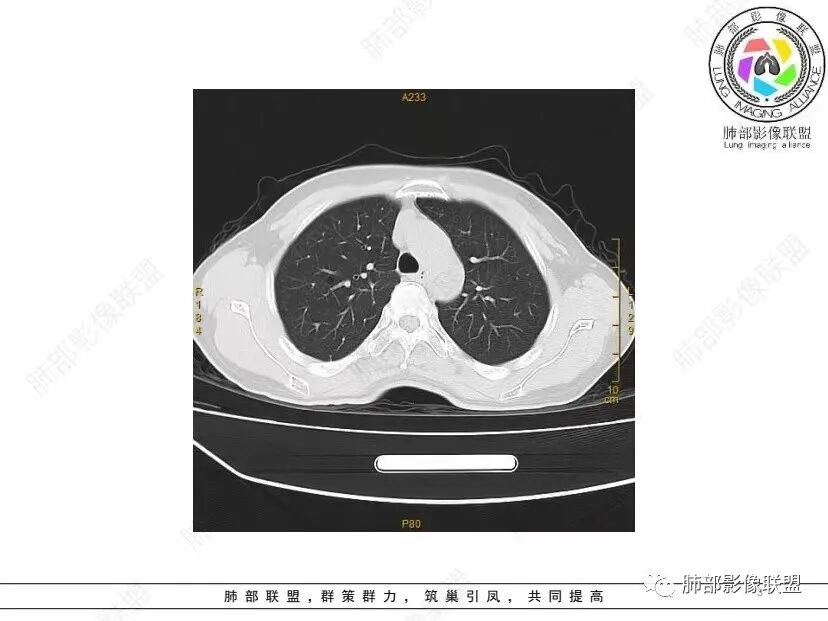

秦化君: 晨读 双肺不均匀散在多发囊状影,大小不等,部分囊形态欠规整,壁薄均匀,部分囊胸膜下平行。双肺少许斑片状磨玻璃影,边缘模糊。考虑BHD综合征。鉴别PCP,LIP。

红日初升: 中年女性,双肺多发气囊,背景干净,大小不一,下肺韧带旁较大,考虑BHD,鉴别LIP、LAM

宇宙: 中年女性,两肺多发大小不等薄壁囊状影,两肺纵膈胸膜下分布明显,考虑BHD,鉴别LAM

这个病例目前影像特点,多囊,囊主要位于下肺,胸膜下及小叶核心为主

伴随少许索条,而且这些病灶与囊不一定有相关性

囊的分布,PLCH基本可以排除

囊壁薄且均匀,光滑,形态规则,基本除外恶性

单纯囊,无斑片及其他实性病灶,感染不支持,可能的是:LAM、BHD、LIP

从囊的分布、大小,BHD可能性可能大一些,但是LIP、LAM都可以这样表现,具体诊断应该是这三种之一,影像缩小到这里我觉得就差不多了,结合临床考虑就行,不支持靠影像强下结论。